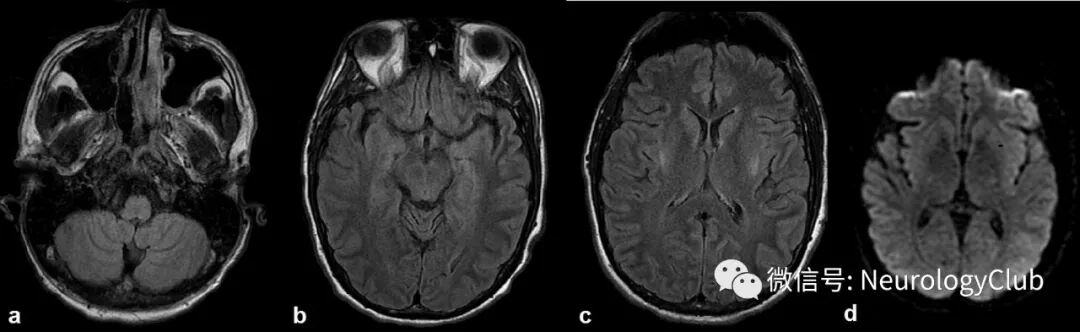

(图2:A-C:FLAIR;D:DWI;可见先前弥散受限和FLAIR高信号病灶几乎完全好转)

开始补充硫胺素后患者意识恢复,再次查体发现患者存在共轭凝视麻痹,水平性眼球震颤和共济失调。在硫胺素替代治疗1周后,眼部异常和共济失调明显好转,复查MRI可见FLAIR上高信号病灶几乎完全消退(图2)。此外,未再见临床或脑电图上的癫痫发作。